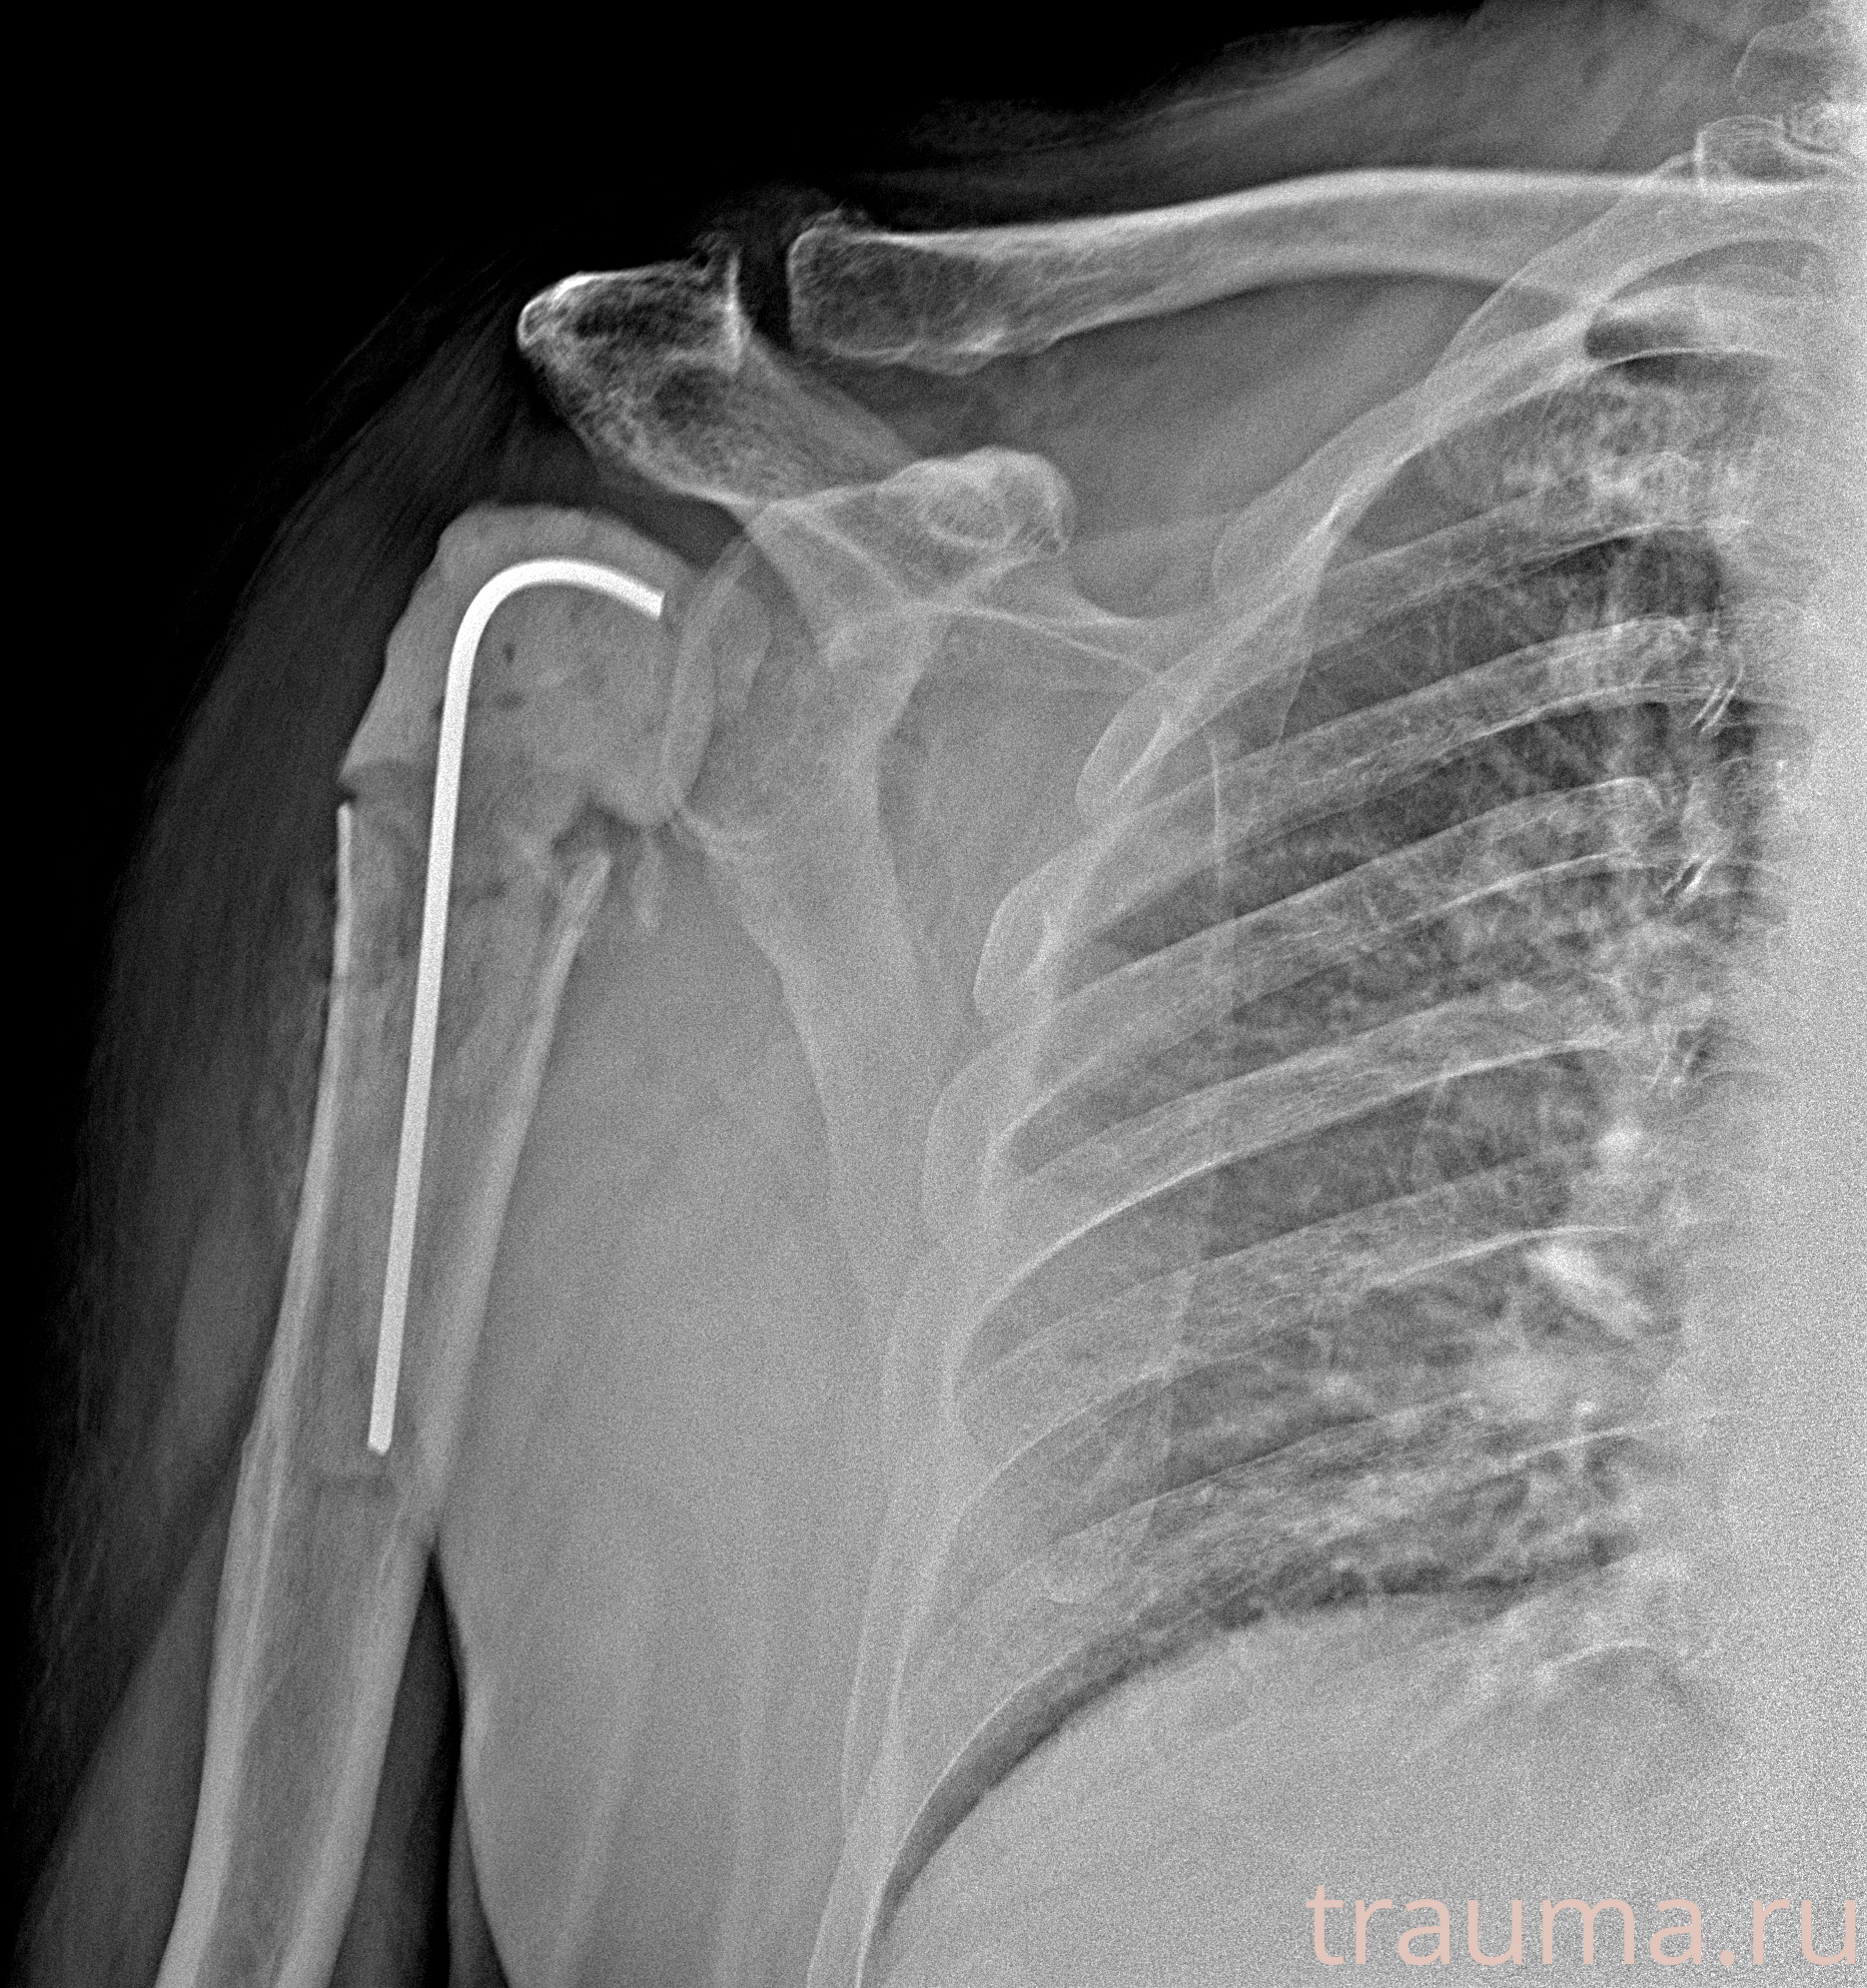

Рентгенограммы